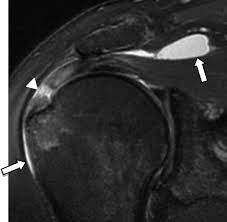

MRI is a non-invasive imaging technique that uses a powerful magnet and radio waves to create detailed images of the internal structures of the body. In the context of subacromial bursitis, an MRI can provide high-resolution images of the soft tissues, including the subacromial bursa, tendons, muscles, and bones in the shoulder.

- Soft Tissue Contrast : MRI excels in differentiating between various soft tissues, helping to identify inflammation, fluid accumulation, and structural abnormalities in the subacromial bursa.

- Detection of Other Pathologies : MRI can also reveal other shoulder pathologies, such as rotator cuff tears or ligament injuries, which may coexist with subacromial bursitis.

- Confirmation of Diagnosis : Both MRI and ultrasound can help confirm the diagnosis of subacromial bursitis by visualizing signs of inflammation, such as fluid accumulation within the bursa.